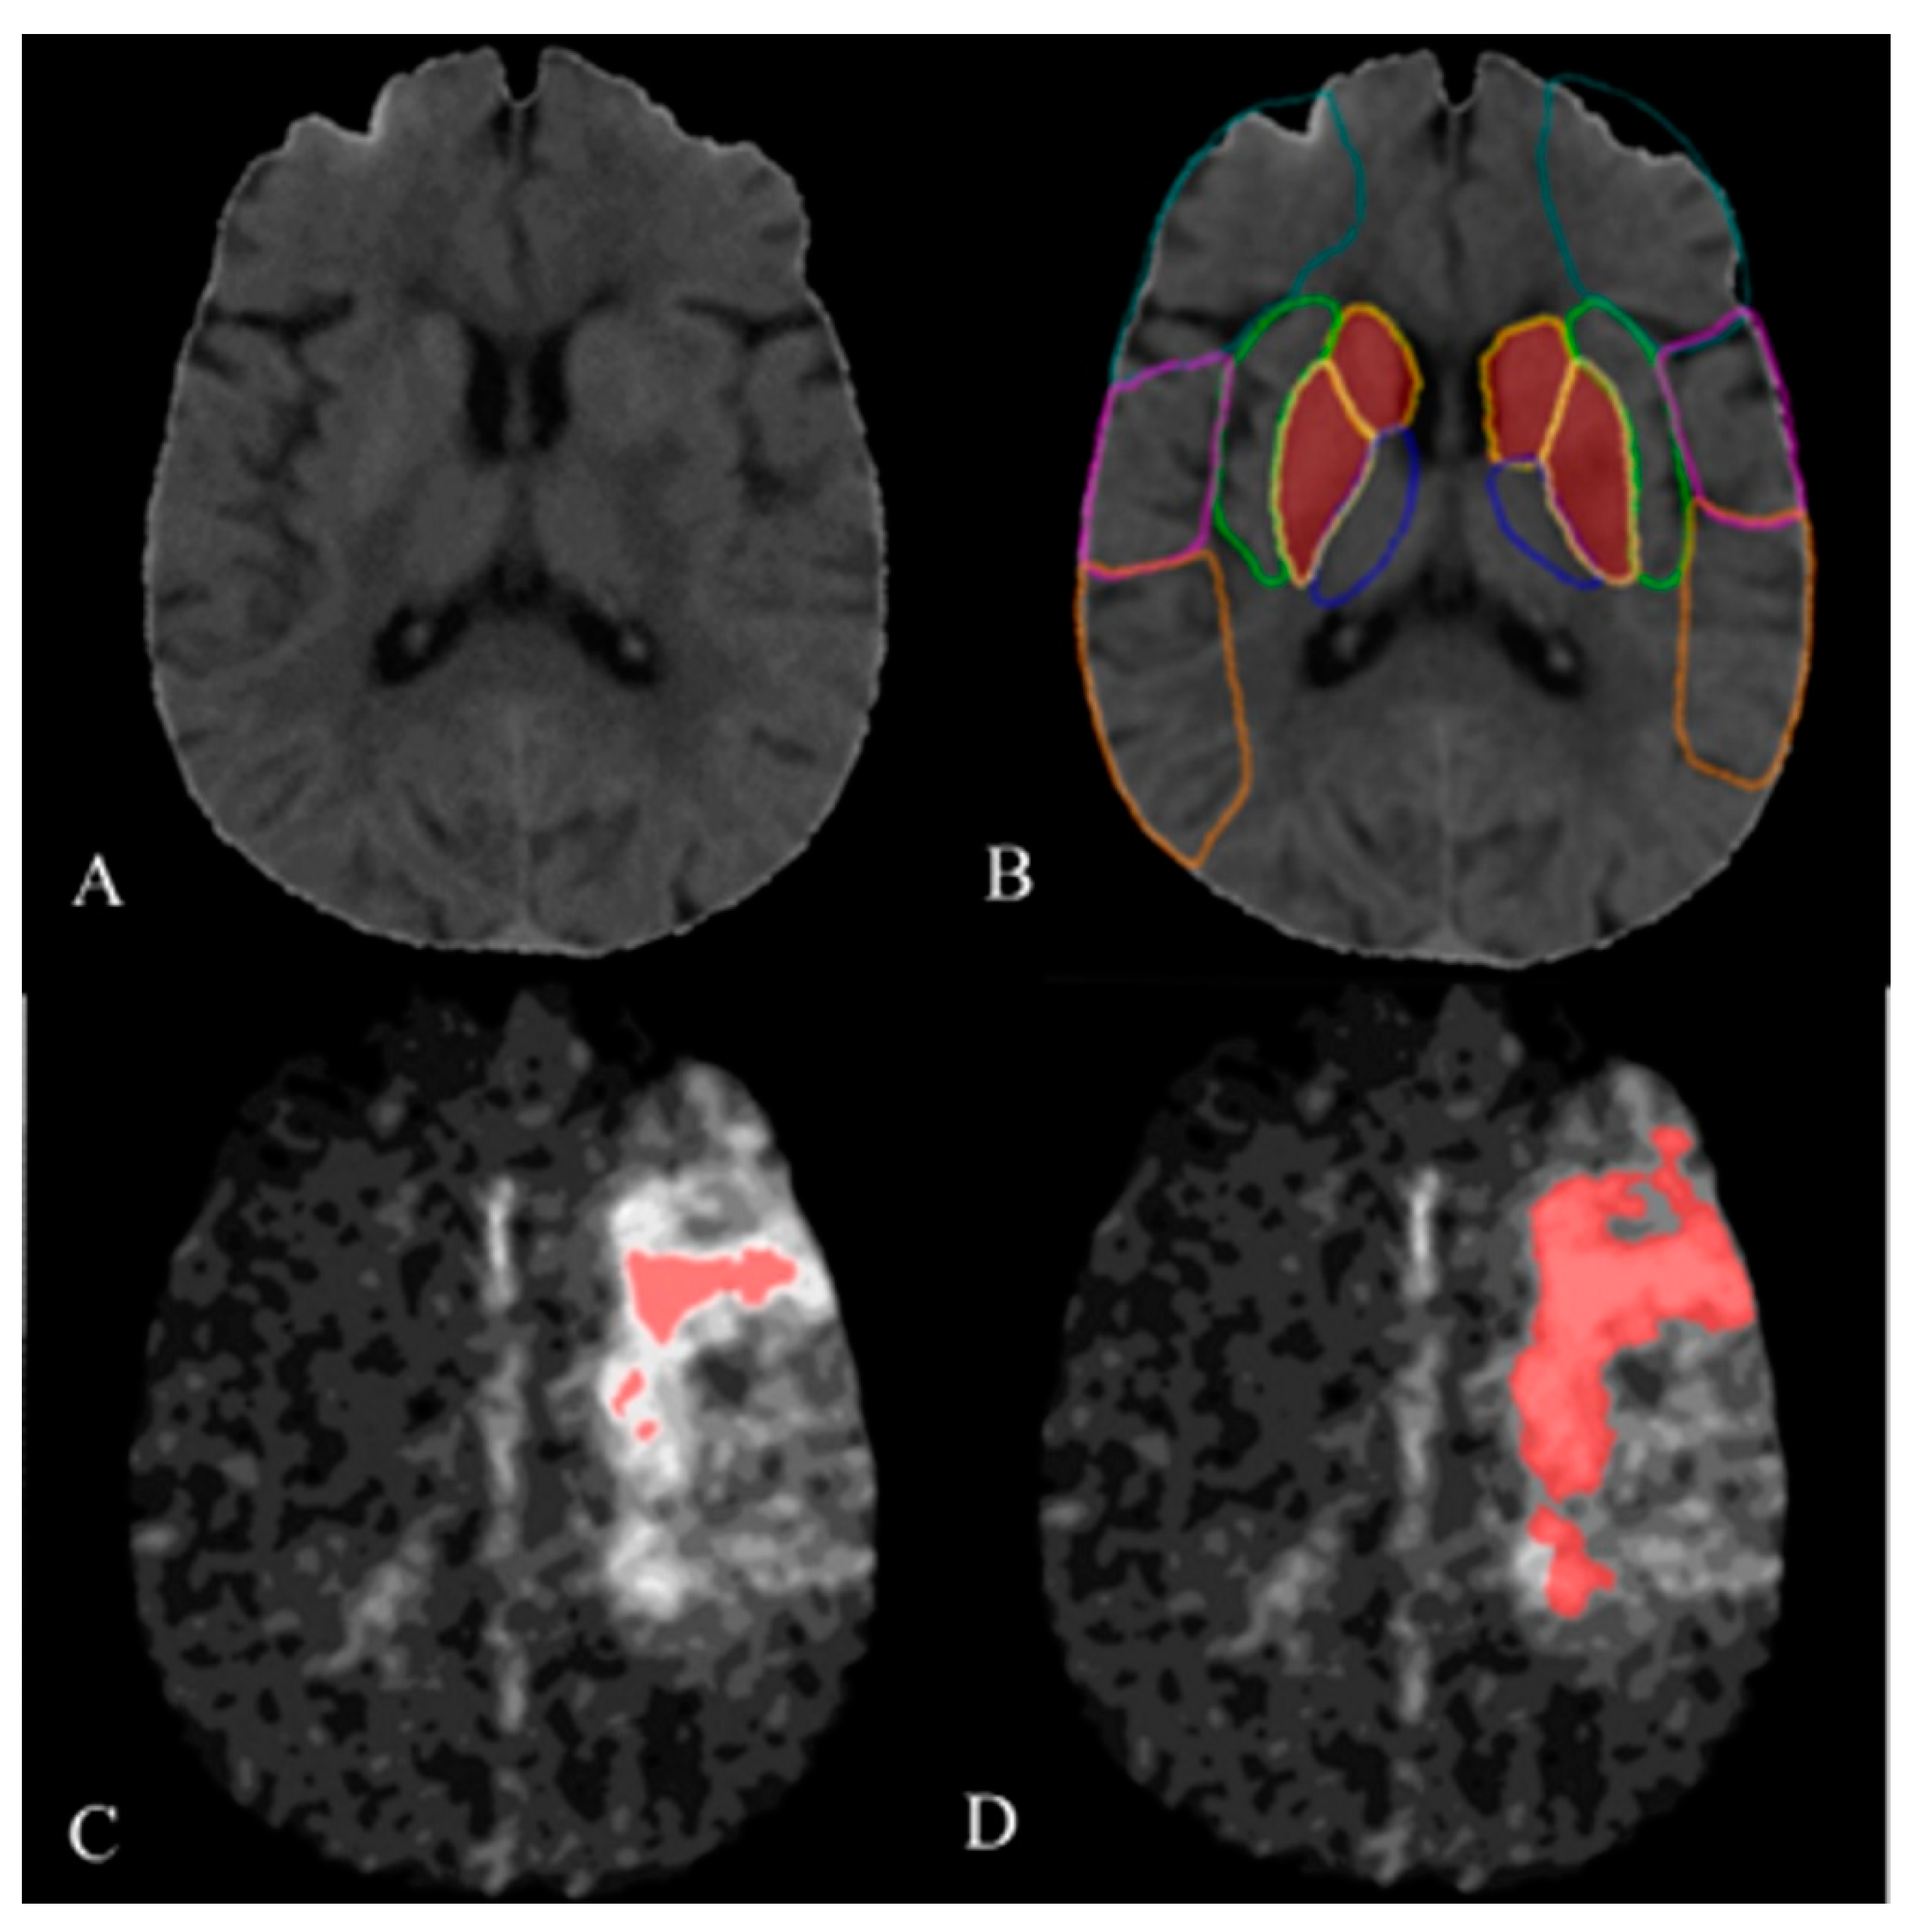

2.3. Image Processing and Analysis